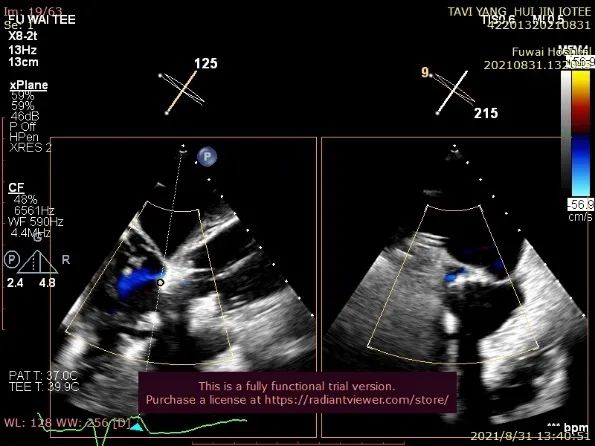

TA-TAVR在全麻和气管插管下进行。经右侧股静脉置入临时起搏器,经右侧股动脉在患者主动脉无冠窦内放置1根6F猪尾导管进行协助定位(图1)。

图1. TEE和放射线显示猪尾导管、临时起搏导线、导丝